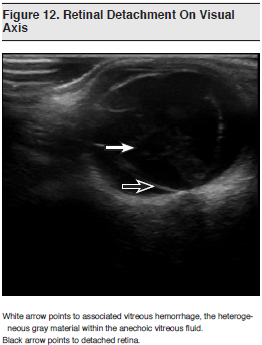

Since the anterior and posterior chambers of the eye contain vitreous fluid, the eye is an ideal acoustic window for ultrasound imaging. Moreover, the contralateral eye can serve as a normal control for the symptomatic eye. Structures such as the anterior chamber, lens, posterior chamber, retina, and optic nerve can all be visualized. As such, conditions such as retinal detachment, vitreous hemorrhage, ocular foreign bodies, lens dislocation, retrobulbar hematoma, and globe rupture can be detected on BUS. (See Figure 12.) Because of the dynamic nature of ultrasound imaging, extraocular eye movements and pupillary response can also be visualized on ultrasound, even when swollen lids prevent direct visualization.101

Although ophthalmologists have been using ocular ultrasound for decades, emergency clinicians have only recently begun to incorporate this tool into their practice.102,103 The current technique involves the high-frequency linear-array transducer (7.5-10 MHz), which is the same probe used for ultrasound-guided vascular access or soft tissue ultrasound. In the largest study of bedside ocular ultrasound performed by emergency physicians, Blavais et al evaluated 61 patients who presented to the ED with a history of eye trauma or an acute change in vision.104 The study physicians included residents and attending emergency physicians who received a 1-hour lecture and 1 hour of hands-on instruction by an ultrasoundfellowship- trained emergency physician. Of the 61 total patients, 26 (43%) were found to have intraocular disorders on BUS. The findings included 9 retinal detachments, 5 vitreous hemorrhages, 3 globe ruptures, 2 lens dislocations, and 1 central retinal artery occlusion. Other findings included papilledema and intraocular foreign body. Ultrasound examinations were followed by either orbital CT or formal ophthalmologic evaluation and were in agreement with the confirmatory studies in 60 out of 61 cases, with a resulting sensitivity of 100% and specificity of 97%. This descriptive feasibility study demonstrated that emergency physicians could accurately detect intraocular disorders using BUS.